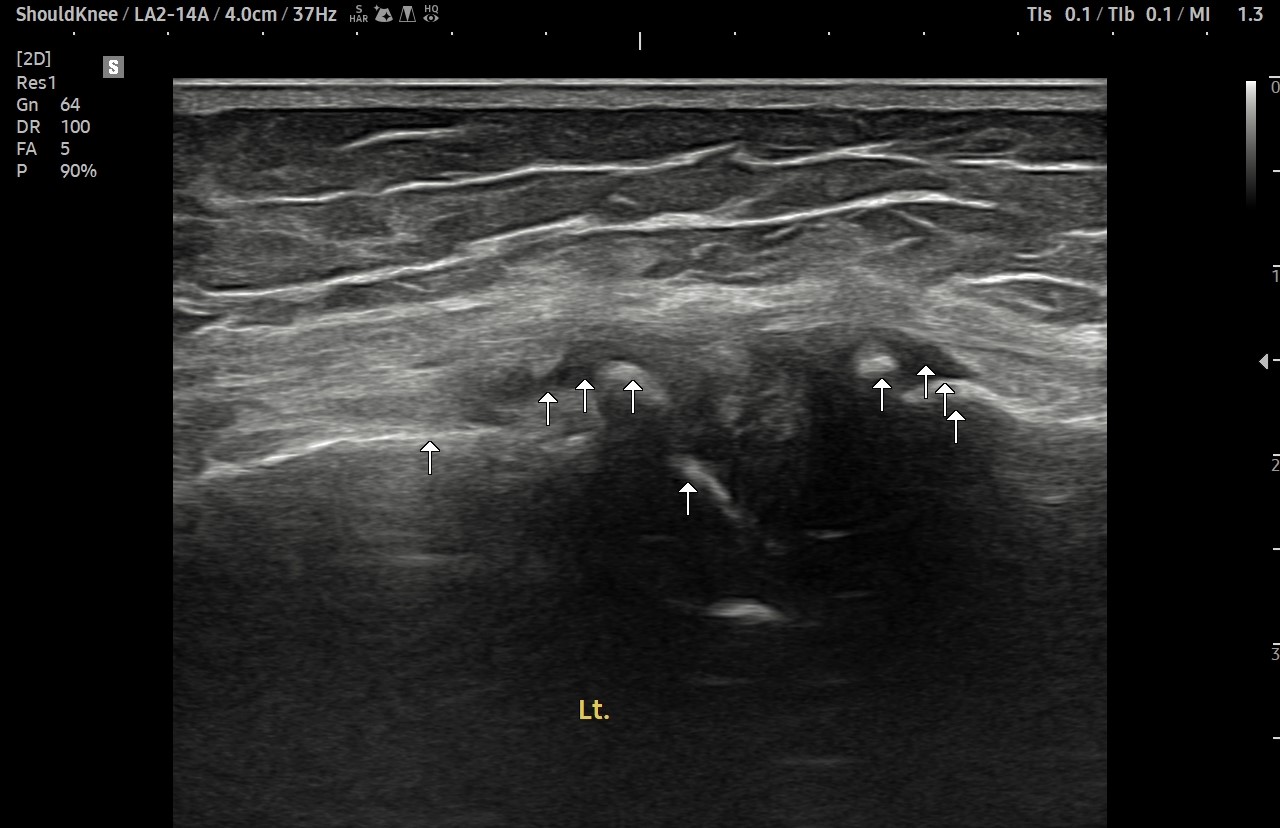

- 치료기간 : 2025. 7. 11 ~ 2025. 8. 26

- 치료횟수 : 8회

치료 전

치료 후